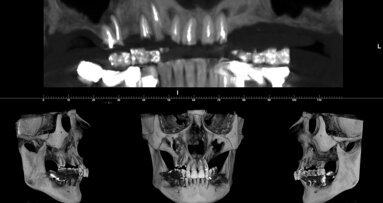

Le ricerche attuali, eseguite in collaborazione con la clinica odontoiatrica dell’Ospedale San Raffaele, Università Vita e Salute, si concentrano sul comportamento istologico dei diversi innesti in una condizione clinica modello quale è il rialzo di seno mascellare (Figg. 1a, 1b). La diversa interazione cellulare mostrata dagli innesti eterologhi a collagene preservato rispetto a quelli trattati per via termica suggerisce che sia possibile osservare differenze significative nel loro rimodellamento qualora essi siano utilizzati in ambito clinico. Di fatto, uno studio clinico randomizzato in cui pazienti con atrofia ossea del mascellare superiore sono stati riabilitati previa esecuzione di rialzo di seno con i due diversi innesti ha mostrato che, a distanza di sei mesi dall’innesto (Figg. 2a, 2b), il sostituto osseo a collagene preservato permette la formazione di una quantità significativamente maggiore di tessuto osseo (46.86% ± 12.81% rispetto 25.12% ± 7.25%) e, simmetricamente, che la quantità di innesto residuo è significativamente minore (11.05% ± 9.27%. rispetto 28.65% ± 9.70%). Il follow-up clinico a tre anni non mostrava differenze significative tra i due innesti.

Si è quindi verificata con uno studio istomorfometrico retrospettivo (Figg. 3a, 3b) l’ipotesi che il sostituto osseo a collagene preservato possa indurre la formazione di una quantità di tessuto osseo in grado di permettere il posizionamento implantare già a un tempo più precoce rispetto a quello che, tradizionalmente, si attende nel rialzo di seno eseguito in due tempi. L’ipotesi si è dimostrata vera, in quanto si è osservato che la quantità di tessuto osseo di nuova formazione osservabile a 3-5 mesi dalla chirurgia rigenerativa quando è utilizzato questo sostituto osseo non è significativamente diverso rispetto a quelle osservabili a 6-8 mesi o a 9-12 mesi dall’innesto stesso. Inoltre, a distanza di 3 anni la percentuale di successo e sopravvivenza implantare non è significativamente differente nelle tre classi temporali; è possibile quindi, utilizzando questa tipologia di innesti, procedere all’inserimento implantare a tempi più brevi (3-5 mesi) rispetto a quelli che si attendono tradizionalmente.